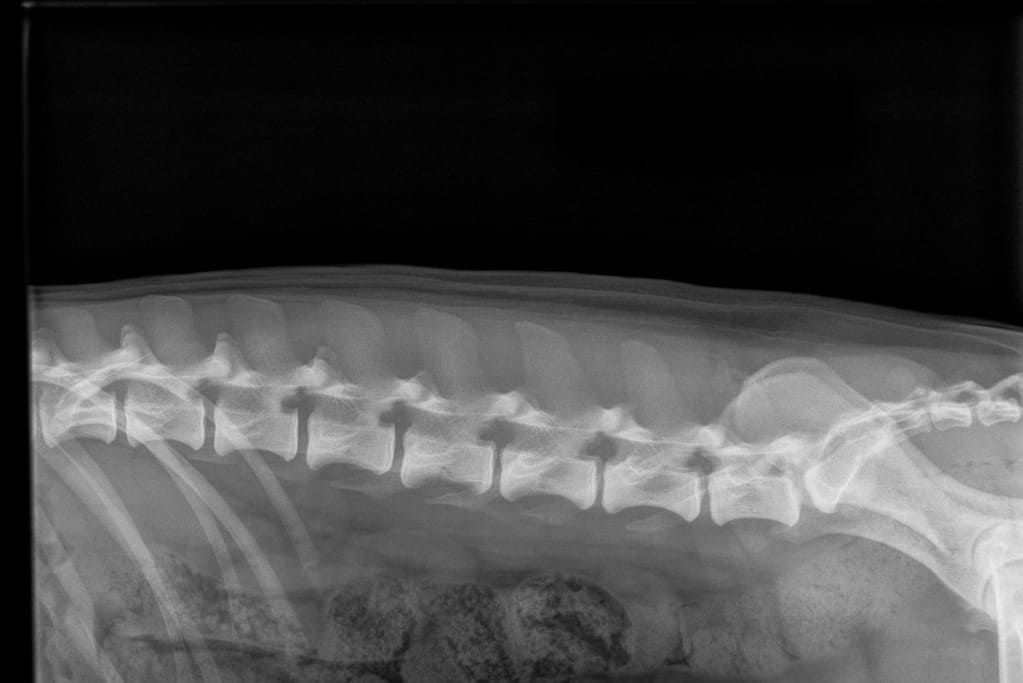

By radiographing the cervical spine, thoracic spine, lumbar spine and sacrum it’s possible to get grading for the LTV, spondylosis (SP) and vertabral anomaly (VA). In Finland for the LTV and VA scoring the must be at least 12 months old and 24 months old for the spondylosis. Instructions for radiography: https://www.kennelliitto.fi/en/forms/idd-ltv-and-spondylosis-instructions-radiography

normal spine

A normal canine spine consists of 7 cervical (C1-7), 13 thoracic (T1-13), 7 lumbar (L1-7) and 3 sacral vertebras (S1-3) resulting the total of 30 vertebras. Calculation starts from first thoracic vertebra (T1). The number of caudal vertebras (CD) vary.